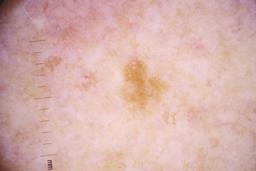

ISIC_4077341

- Challenge 2020: Training

- IP_1969685 IL_9238622

Clinical

| Field | Value |

|---|---|

| acquisition_day | 1 |

| age_approx | 50 |

| anatom_site_1 | Trunk |

| anatom_site_2 | Anterior trunk |

| concomitant_biopsy | False |

| dermoscopic_type | contact non-polarized |

| diagnosis_1 | Benign |

| diagnosis_confirm_type | serial imaging showing no change |

| family_hx_mm | False |

| image_type | dermoscopic |

| lesion_id | IL_9238622 |

| patient_id | IP_1969685 |

| personal_hx_mm | True |

| sex | male |